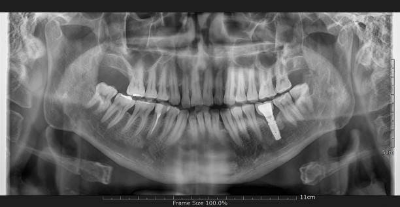

3-3. 신경 손상

드물지만 임플란트가 신경과 너무 가까이 식립되면 감각 이상이나 저림 증상이 나타날 수 있습니다. 이런 경우에는 환자가 매우 큰 불편을 겪을 수 있으며, 신속한 진단과 처치가 필요합니다.

환자분(김ㅇ진님)은 #34 부위에 임플란트 수술을 받으셨습니다. 수술은 약 30분 만에 순조롭게 마쳤습니다.

새벽 2시까지도 감각 이상이 지속되어, 다음날 아침 첫 진료 시간에 내원하시도록 안내했습니다. 검사 후 픽스처를 2mm 짧은 것으로 교체하는 재수술을 진행했고, 다행히 5시간 만에 입술 감각이 회복되었습니다.